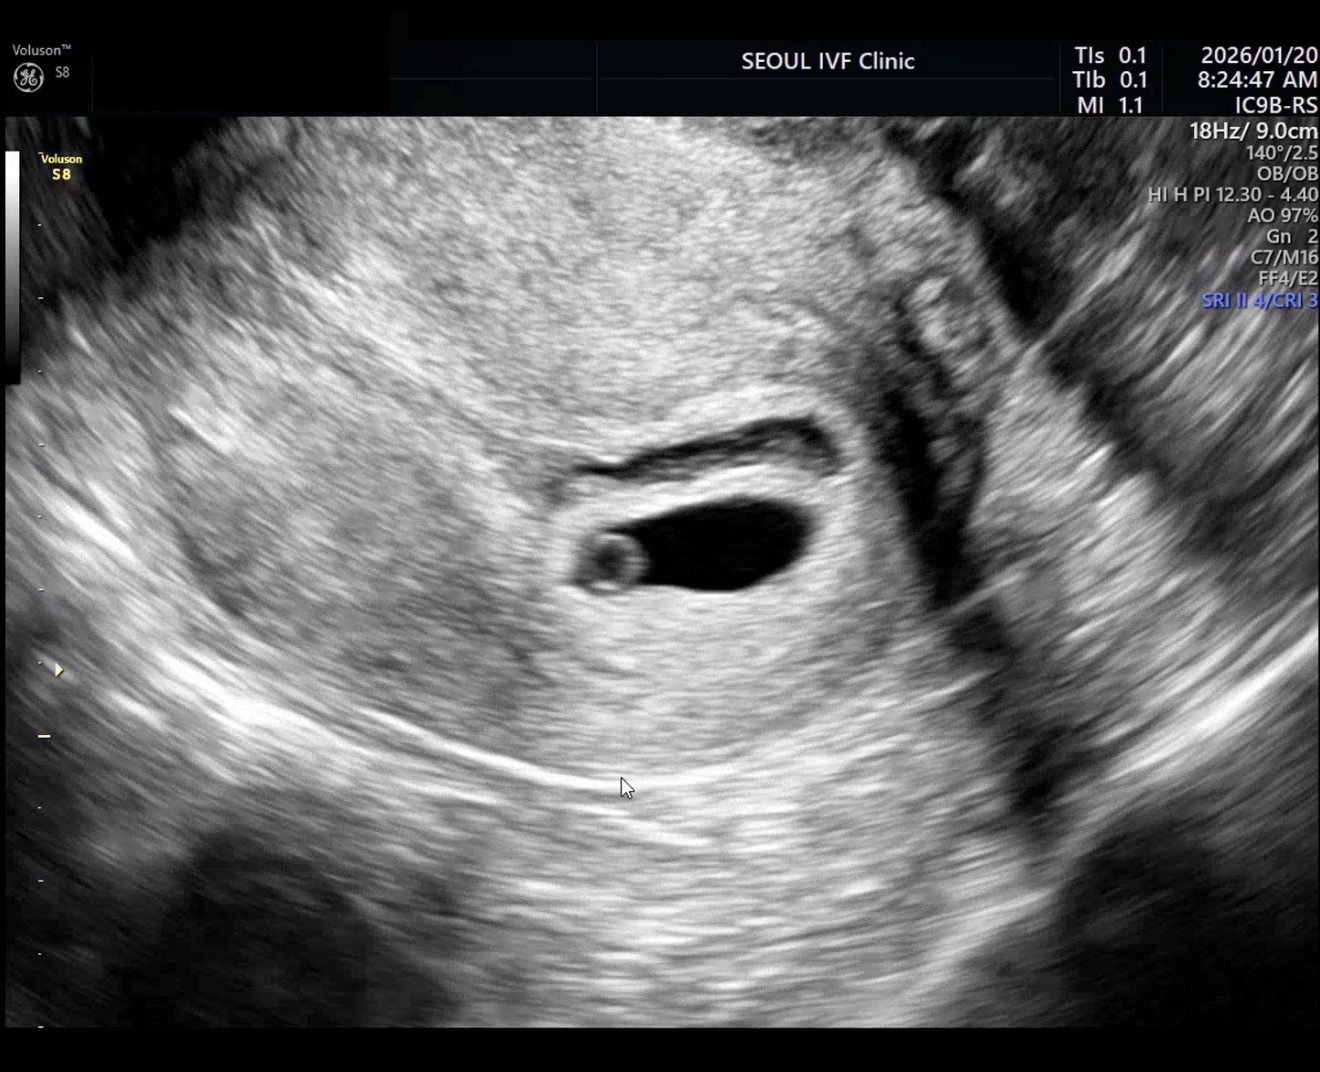

기다림 끝에 마주한, 가장 뭉클한 한 장면 - 희망나눔